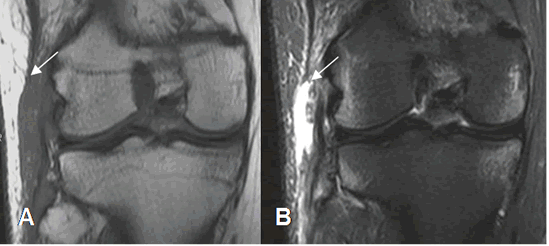

Fig 122. Esguince del LCL.

A y B: RM coronal en STIR. Cambios inflamatorios rodeando el LCL, el cual permanece intacto, por esguince.